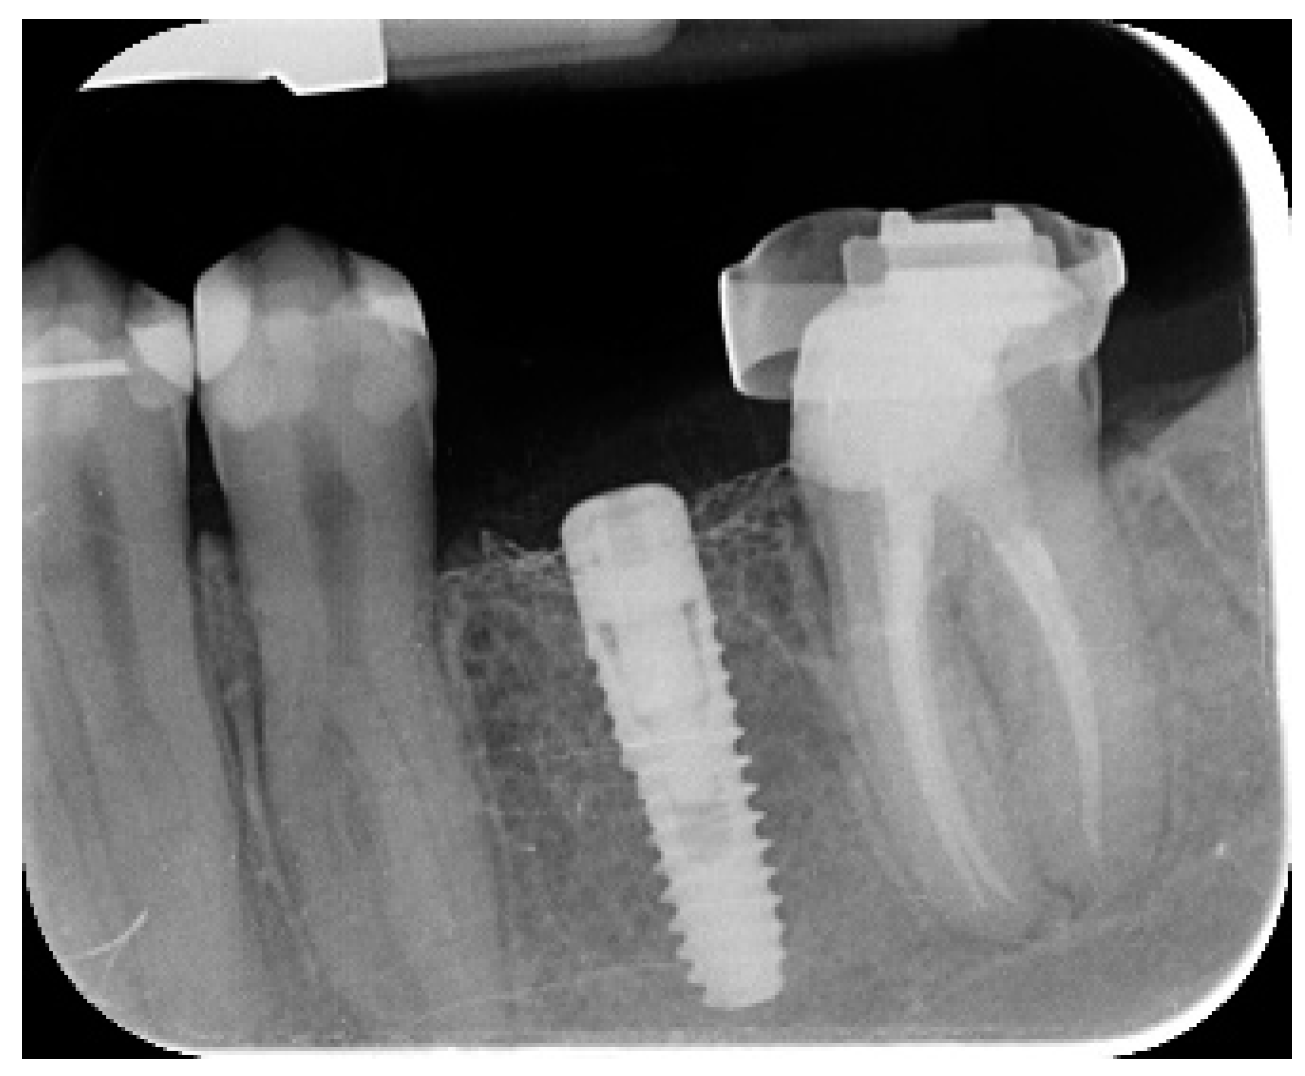

- Marginal bone level changes were assessed by digital periapical radiographs (Digora Optime; Soredex, Tuusula, Finland) using the parallel technique and commercially available film holders. Three time points were evaluated, at implant placement (baseline), immediately after the insertion of the restoration, and one year after loading. The averaged mesial and distal distances from the most coronal margin of the implant and the first bone-to-implant contact was measured to the nearest 0.01 mm and taken as the marginal bone level. The difference in levels between time points was taken as marginal bone loss (MBL).

- Horizontal bone augmentation was evaluated at the CBCT scans, 1 mm below the original bone crest. The volumetric data were superimposed using the adjacent teeth as reference points, and a new generated set of DICOM data was stored as a separately files. Measures were taken before and after the treatment, and the difference of these two measurements was taken as horizontal bone augmentation (Figure 9).